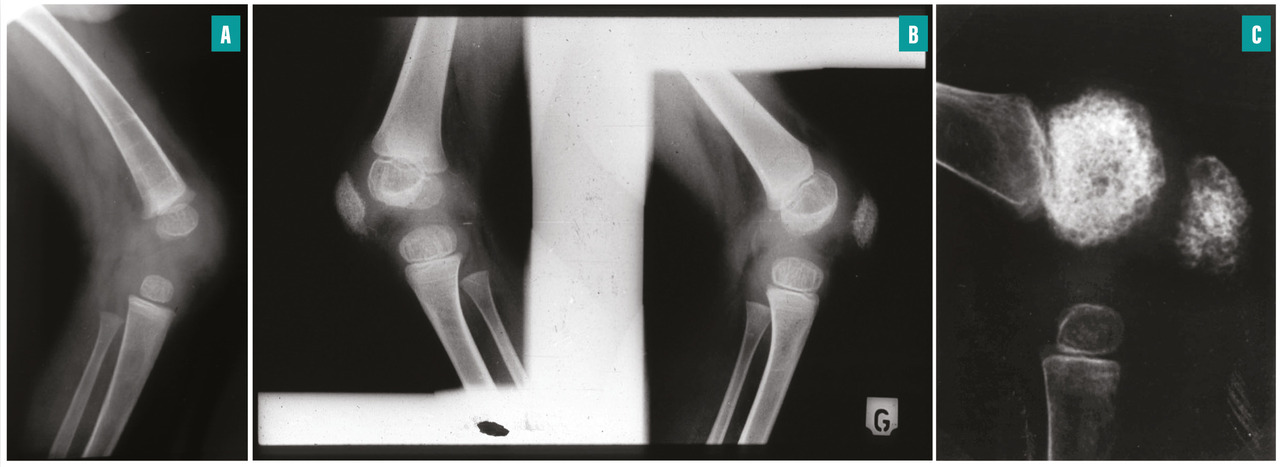

fig. 2 ). Cette atteinte articulaire est d’autant plus sévère et invalidante qu’elle débute précocement. Elle s’accompagne de contractures, d’impotence fonctionnelle et parfois d’intenses douleurs. Cette hypertrophie est secondaire à des remaniements épiphysaires et métaphysaires des os longs et à une hypertrophie des cartilages de croissance. Une hypertrophie caractéristique de la rotule est fréquente. Radiologiquement, les métaphyses sont élargies et irrégulières, en forme de cupule. Les épiphyses sont élargies et irrégulières, elles peuvent prendre un aspect « grotesque », en « mie de pain ». Les noyaux d’ossification de la rotule apparaissent précocement et ont un aspect inhomogène (fig. 3 ). Une ostéoporose modérée est fréquente.

Les atteintes articulaires sont d’expression très variable. Certains malades se plaignent d’arthralgies pouvant s’accompagner d’un gonflement articulaire transitoire. Elles touchent en priorité les grosses articulations telles que les genoux, les chevilles, les coudes, les poignets mais peuvent aussi concerner les extrémités telles que les mains et les pieds. Ces atteintes sont le plus souvent symétriques. Elles n’évoluent vers aucune modification ostéoarticulaire. Dans un tiers des cas, une arthropathie apparaît et se caractérise par une hypertrophie symétrique des grosses articulations, en particulier des genoux, des chevilles, des poignets et des coudes (Atteinte du système nerveux central